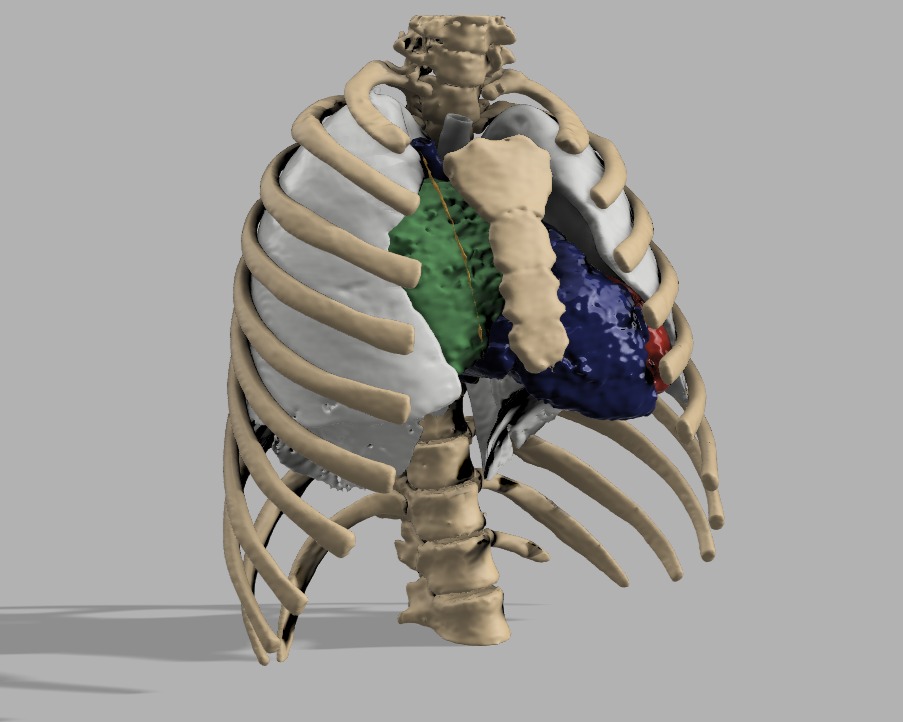

Anomalía del retorno venoso

Biomodelo cardíaco desarrollado para comprender una anatomía compleja, anticipar el abordaje quirúrgico y facilitar la comunicación del caso entre el equipo médico.

Anomalía del retorno venoso

Biomodelo cardíaco desarrollado para comprender una anatomía compleja, anticipar el abordaje quirúrgico y facilitar la comunicación del caso entre el equipo médico.